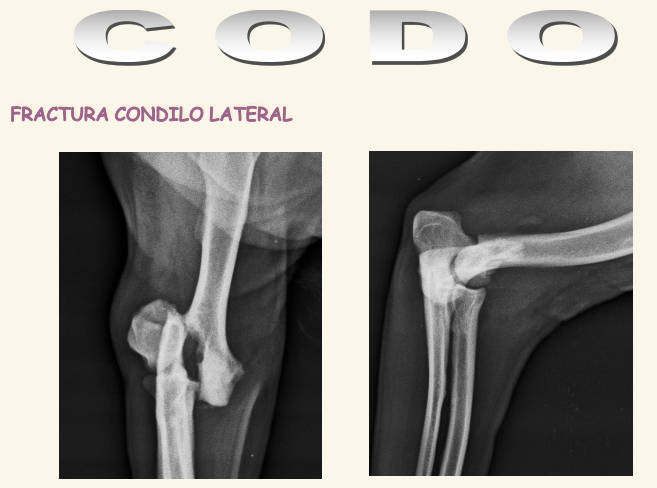

Codo

El condilo medial es mas fuerte que el lateral. Se dan fracciones en T o en Y. Luxacicones son mas dificiles que en codo

Existe la displasia del codo

- FCM: Fragmentación del Coronoides Medial, una de las lesiones típicas de displasia de codo

- NUPA: No Unión del Proceso Anconeo

- OCD: Osteocondritis disecante del condilo medial

- Incongruencia, mala articulacion de los 3 huesos.

- Se suele ver esclerosis subcondral que es la presencia de distinta densidad en el hueso bajo la articulación